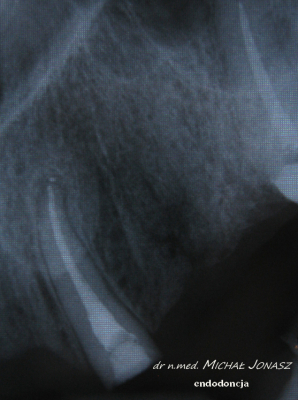

EXAMPLES OF ROOT CANAL TREATMENT PERFORMED BY OUR TEAM

Root canal treatment becomes necessary when the pulp of the tooth is attacked, that is, the tissue filling its interior, which is composed of blood vessels and lymphatic vessels as well as nerve fibers. In some cases, it happens that the tooth does not give pain, and yet there is an irreversible bacterial infection of the pulp. In most cases, patients requiring root canal treatment complain of acute pain in the affected teeth. Endodontic treatment is also necessary in some cases of tooth injury. This method of treatment is also sometimes used due to prosthetic indications. Infected dental pulp and pathological changes occurring in it are sometimes visible on the radiological image, which is performed before the procedure. Thorough cleansing, chemo-mechanical treatment of the root canal and its tight filling, for which special microscope is used, in the vast majority of cases leads to remission of bone changes and bone regeneration.